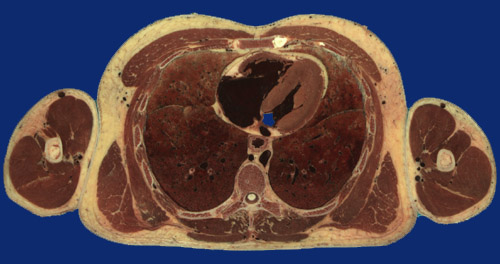

Identify the following regions in the image above: Latissimus dorsi - Serratus anterior - Sacrospinalis - Trapezius - Pectoralis major - Body of Sternum - Left ventricle - Right ventricle - Esophagus - Descending aorta - Left upper lobe - Left lower lobe - Right middle lobe - Right lower lobe - Vertebral body - Spinal cord